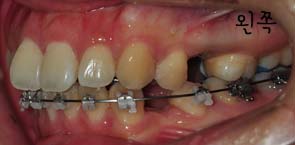

저는 스크류 2개를 입천장에 심어서 이것을 킬본교정장치와 연결아서 당김으로써 앞니가 들어가는것에 효과를 주도록 하였는데요

사진과 같이 보시면 입천장에 스크류가 심어졌을때의 모습이 보이시나요? 사진과 같이 두개의 스큐르를 심은후 고무로된 연결고리로 연결하여 킬본교정장치에 걸어서 당기고 당기고~ 를 해주는겁니다 *,*